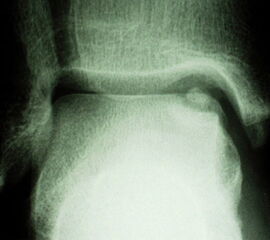

Laterale Läsionen entstehen meist durch ein akutes Trauma mit dorsalflektiertem und invertiertem Sprunggelenk, was zum Anschlag des Talus an der Fibula führt. Diese Läsionen sind meist vorderen Anteil der Talusrolle zu finden 7. Mediale Läsionen sind eher mit wiederholten Supinationtraumata verbunden oder treten aus ungeklärter Ursache auf. Insgesamt sind mediale Läsionen häufiger und meist im mittleren und hinteren Drittel des Talus zu finden 7. Laterale Läsionen sind von ihrer Konfiguration her eher flach und „waffelförmig“ (wafer-shaped) (Abb. 1), während sich mediale Läsionen eher tiefer und „tassenförmig“ (cup-shaped) darstellen (Abb. 2).

Anerkannte Klassifikationen (Tabelle 1) zur stadiengerechten Einteilung der Läsion können bei der Entscheidungsfindung hilfreich sein. Die klassische Röntgeneinteilung osteochondraler Läsionen geht auf die 1959 publizierte Klassifikation nach Berndt & Harty zurück 1 (Abb. 10). Dabei werden vier Stadien beschrieben. Im Rahmen der arthroskopischen Diagnostik empfiehlt sich die Klassifikation nach Guhl 32, welche sich der Klassifikation nach Berndt & Harty richtet. Loomer, sowie Scranton und McDermott fügten der Röntgeneinteilung später ein fünftes Stadium hinzu um die OCL mit subchondraler Zystenbildung zu erfassen 2930. Für das MRT entwickelten Dipaola et al. 31 eine Klassifikation für osteochondrale Läsionen in vier Stadien, basierend auf der radiologischen Einteilung nach Berndt und Harty. Für rein chondrale Läsionen wird standardmäßig die ebenfalls vier Stadien umfassende Klassifikation nach Outerbridge verwendet 33. Hier kennzeichnen die Stadien III und IV tiefgreifende Knorpelerosionen bzw. Knorpelkrater mit freiliegendem Knochen. Diese Klassifikation kann MR-tomographisch oder intraoperativ verwendet werden, wobei die Beurteilung im MRT durch die geringe Dicke des talaren Gelenkknorpels erschwert ist. Von Ferkel u. Sgaglione wurde eine CT-Klassifikation in ebenfalls vier Stadien veröffentlicht 11. Im Unterschied zu den bisher erwähnten Klassifikationen beschreibt das Stadium 1 zystische subchondrale Veränderungen ohne Kommunikation zum Gelenk, während beim Stadium 2 die Kortikalis aufgebrochen ist. Die Stadien 3 und 4 entspricht dann wieder der Klassifikation nach Berndt & Harty.